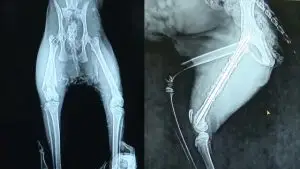

...回到醫院,拍片後發現,黑貓媽媽的大腿果然已經骨折。

雖然,它一直不願進食,身體也有貧血的狀況,若是進行手術,風險很大,但是,傷情嚴重,不得不冒險手術。

經過四個多小時的手術,黑貓媽媽總算是從鬼門關爬了回來,然而,喪子之痛讓它依然神情落寞,毫無生氣。